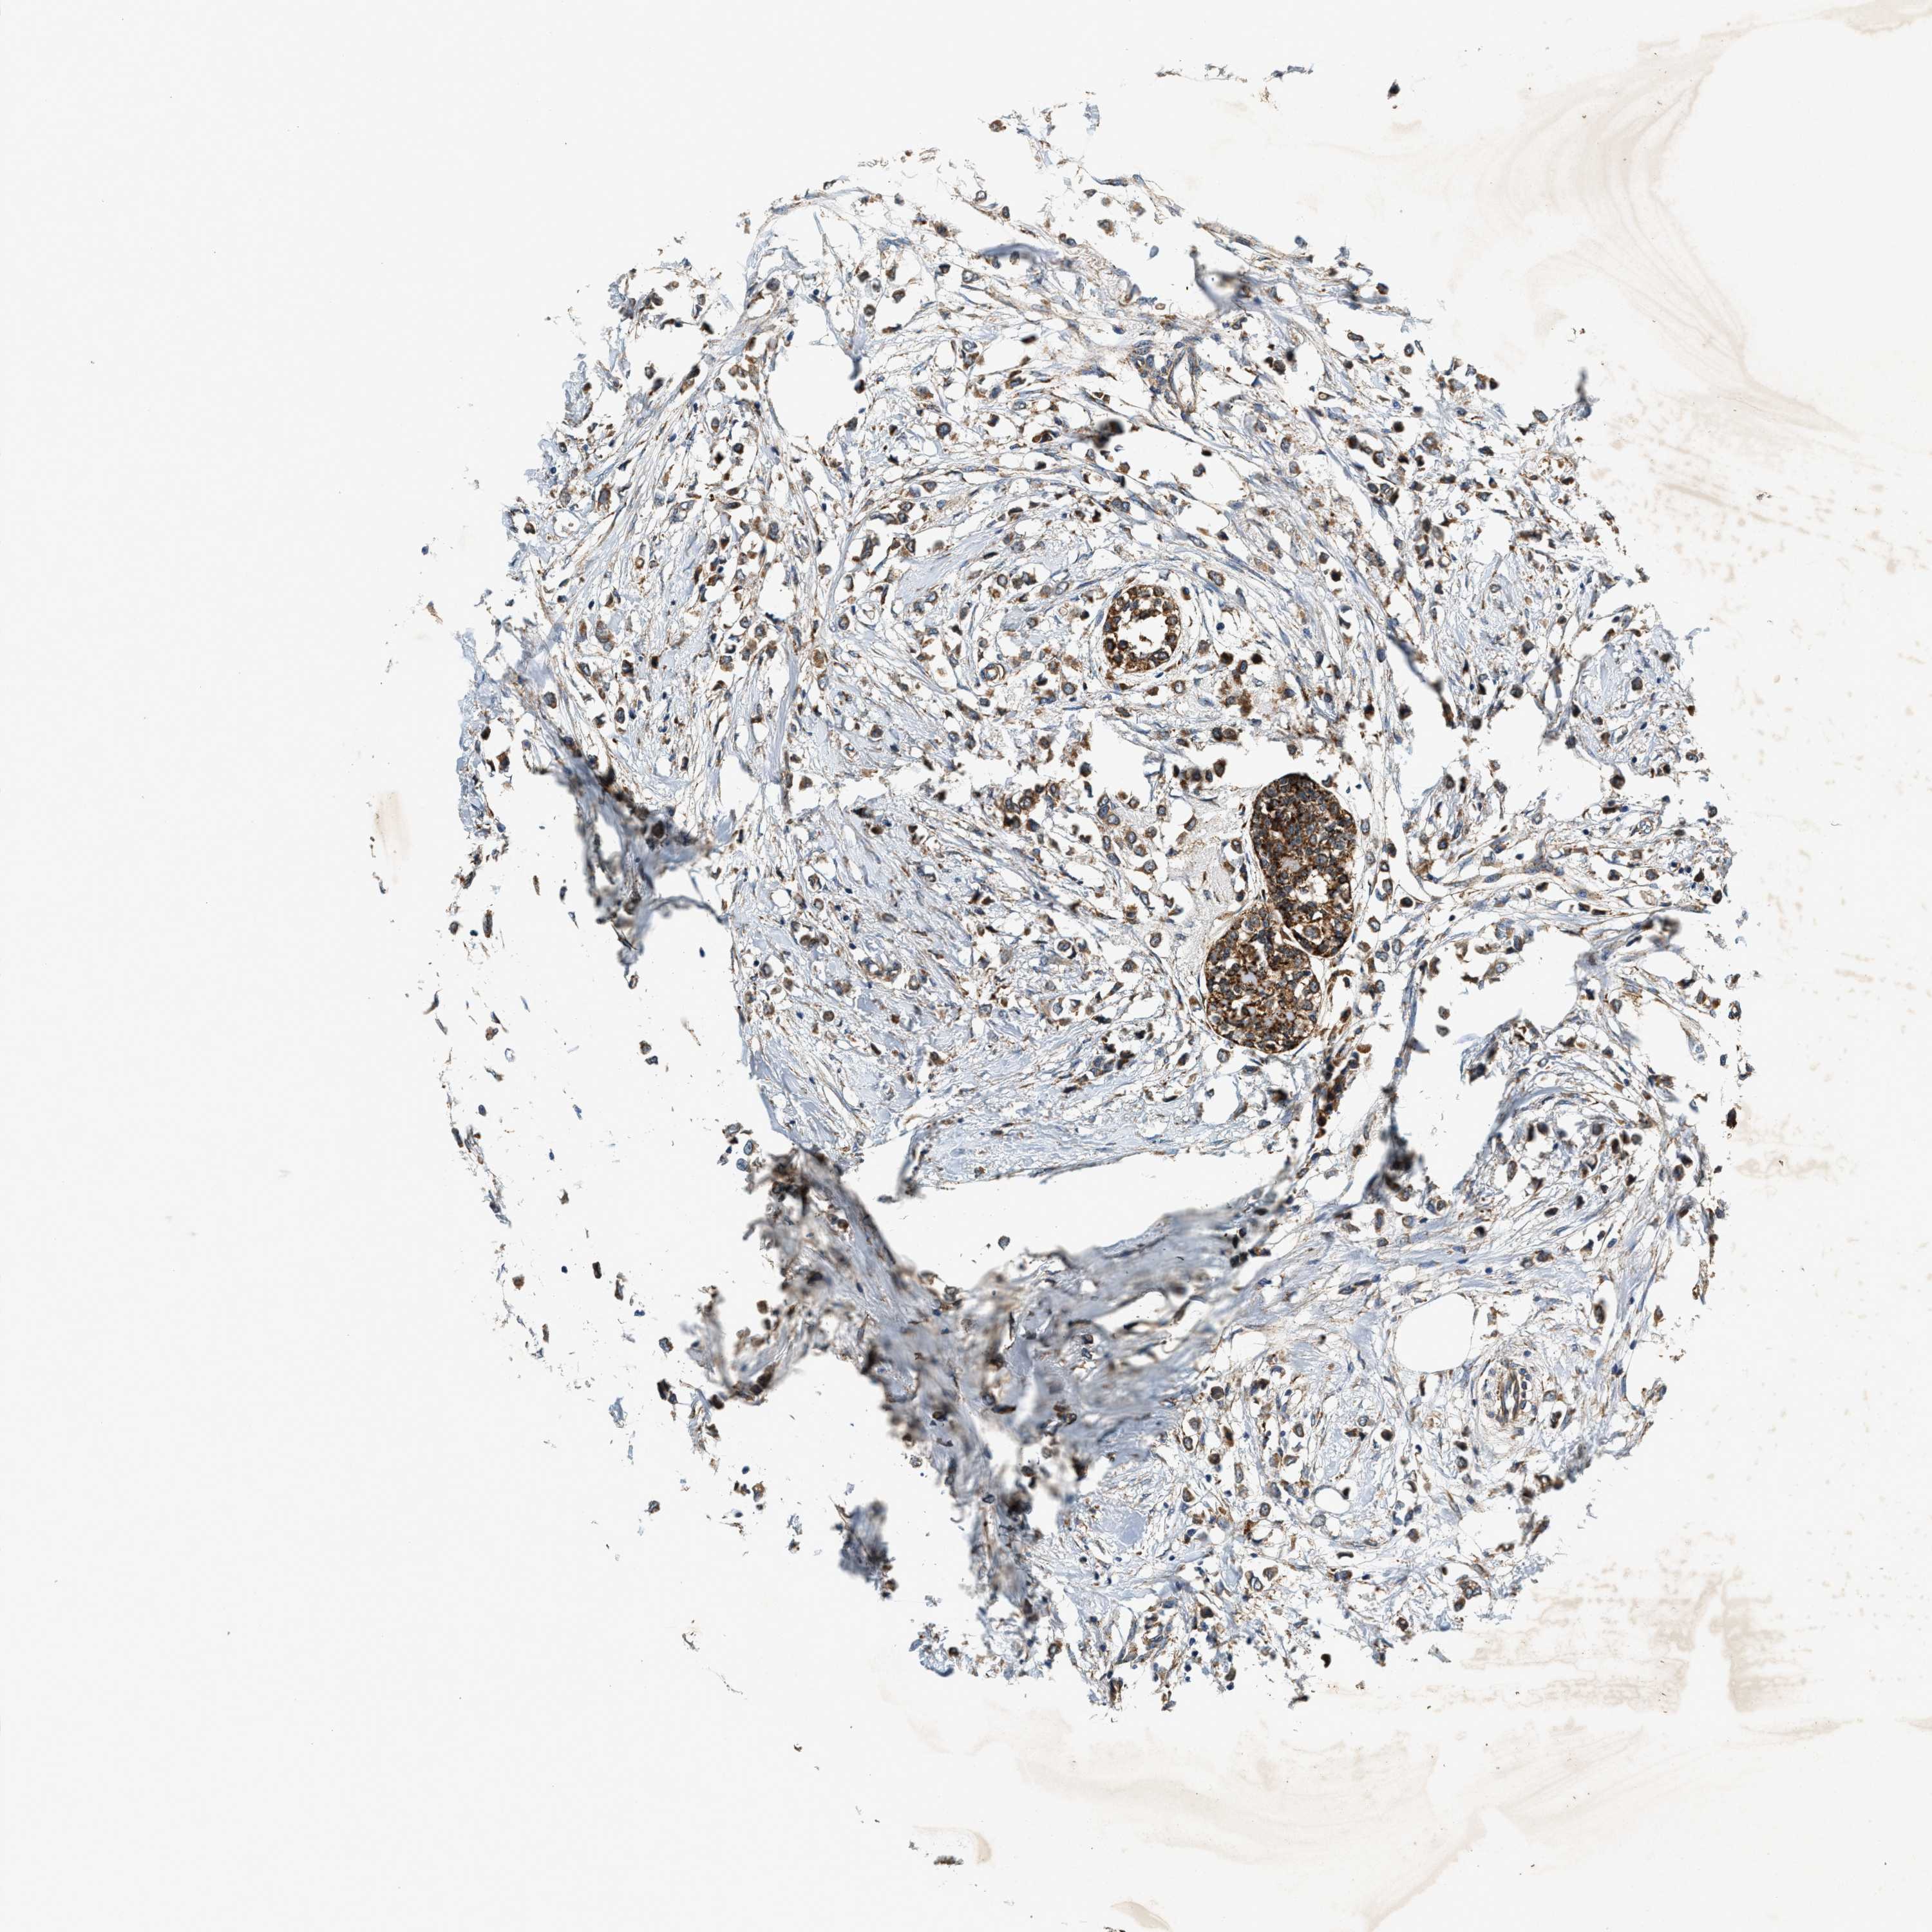

CANCER BREAST CANCER Show tissue menu

BRCA TCGA BRCA VALIDATION PROTEIN EXPRESSION